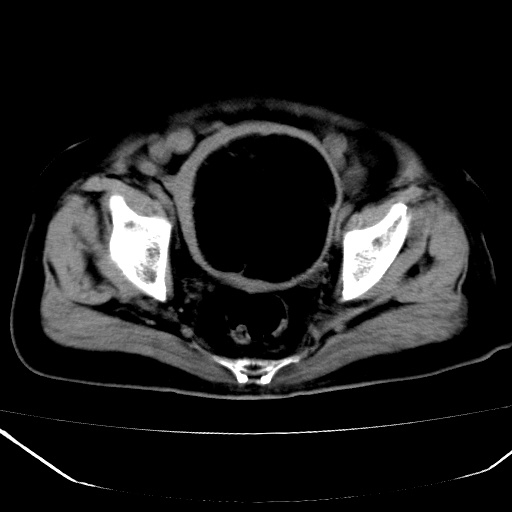

患者,女,74岁,无不适,b超示盆腔包块。

子宫前上方巨大脂性肿物,肿物边缘为较厚软组织密度影,其内缘欠光整,脂性密度中央见结节状软组织密度影“漂浮”,肿物与子宫前壁关系密切,考虑1脂肪瘤2皮样囊肿3肌瘤脂样变

ct值-90hu